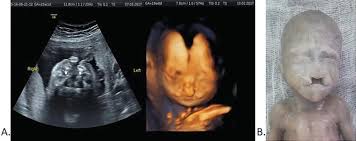

If the 2D ultrasound does not demonstrate two nasal bones then 3D ultasound may be useful. An ultrasound scan There is no risk to the baby from either of these procedures. October 15 2018 Shane Dale According to the National Down Syndrome Society NDSS during the normal fertilization of a womans egg by a mans sperm the resulting nucleus of each cell in a fetus contains 23 pairs of chromosomes half of which are inherited from each parent.

For this reason 3D ultrasound reconstruction of the nasal bone and other facial bones is useful. At this stage the babys legs arms fingers and toes should be fully formed. Mothers should not be encouraged to have an ultrasound called a.